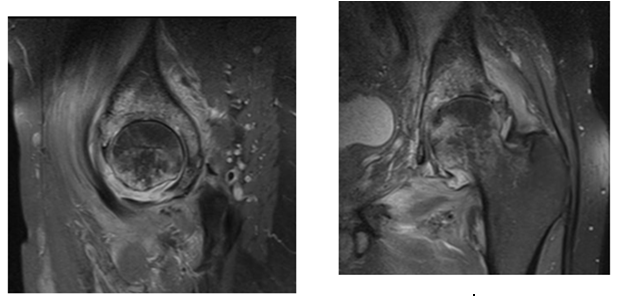

The second case is a 42 year old male patient who had a psoas muscle tear while playing football 3 weeks before consultation that complicated with psoas infection and bad response to antibiotics. MRI showed a clear collection in iliac fossa and advanced articular damage associated to synovitis.

Two stage treatments consisted in an initial surgery through a posterior approach, debridement of inflammatory tissues, neck osteotomy and acetabular reaming adding a temporal non-articulated antibiotic impregnated cement spacer for the resected femoral head. 6 weeks after surgery when intravenous antibiotic treatment was completed and laboratory inflammatory parameters were controlled, a second stage surgery was planified: Conversion to a hybrid arthroplasty for the first case and a non cemented total hip arthroplasty for the second case (Figure 1) (Figure 2).

Figure 2: 44 year male patient. A and B images show hip articular damage, C, D, E, F MRI shows a purulent collection and articular effusion. G image of the spacer H and I postoperative x-ray showing the non cemented total hip arthroplasty. Differed anatomy showed chronic inflammation compatible with osteomielitis for both cases, staphylococcus aureus meticilin resistant organism was isolated. Harris Hip Score of 96 at 2 year follow up, infection markers controlled, and no complications were reported.